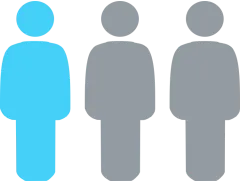

1 IN 3 PATIENTS

diagnosed with depression don’t achieve adequate results with standard therapy.

They’re often labeled “treatment-resistant”… leading to higher doses or additional medications.

1 IN 3 PATIENTS

diagnosed with depression don’t achieve adequate results with standard therapy.

They’re often labeled “treatment-resistant”… leading to higher doses or additional medications.

A significant subset of patients diagnosed with depression do not respond to standard therapies.

They are often labeled “treatment-resistant,” leading to medication escalation rather than deeper investigation.